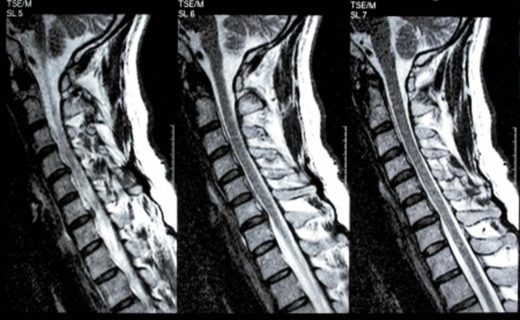

This means that our specialists are not only experts within physiotherapy but also have received extensive training in medical diagnostic methods and management of musculoskeletal disorders.